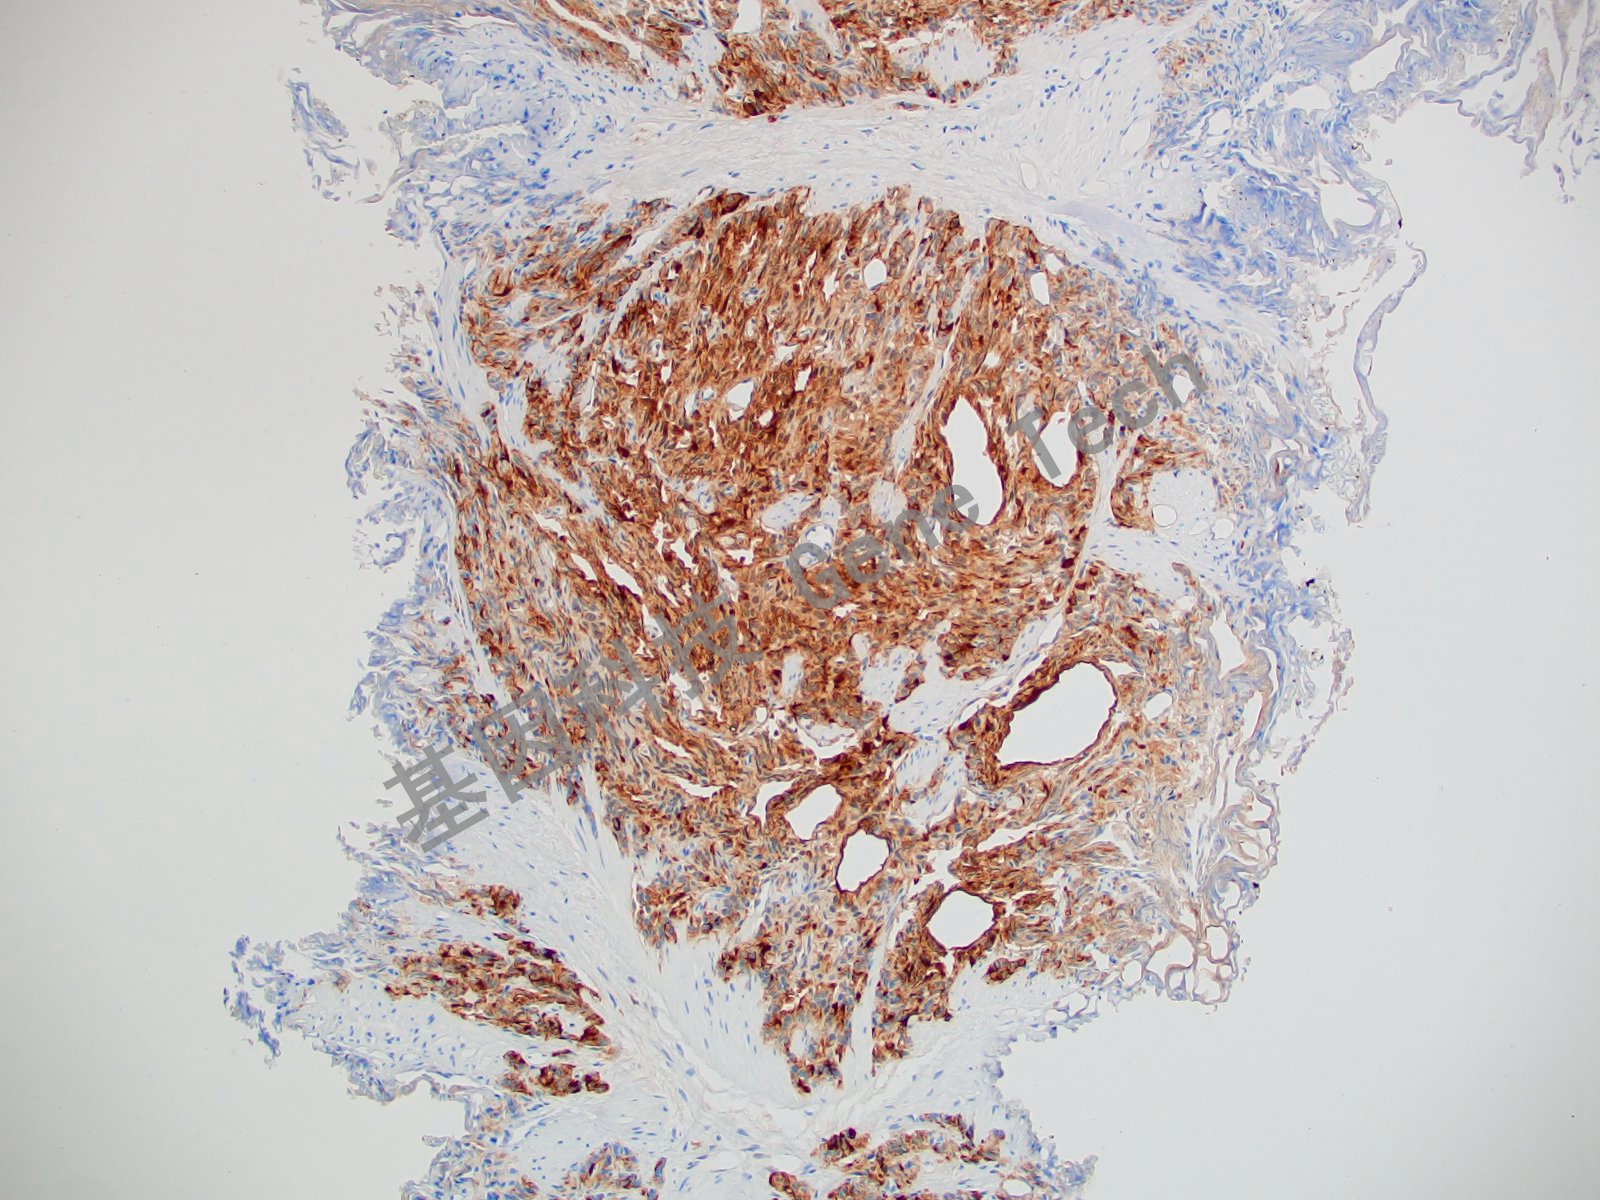

前列腺癌石蜡切片,用 Survivin(GT2048)染色,细胞浆/细胞核阳性,DAB 显色。